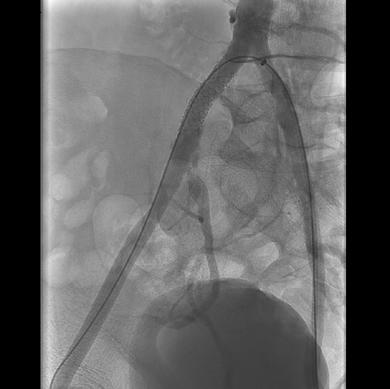

The use of degradable microspheres for uterine fibroid embolization (UFE) have demonstrated “excellent” infarction rates and fibroid volume reduction according to a recent study.

PRESENTED AT THE EUROPEAN Conference on Embolotherapy (ET; 11–14 June, Porto, Portugal), speaker Paul Lohle (ElisabethTweesteden Ziekenhuis, Tilburg, Netherlands) said the shift from permanent to temporary embolic material is of growing interest amidst increasing concern and questions—not only among patients— over “foreign materials and plastics” remaining in the body post-UFE. Lohle states that worry stems from the potential immune reaction to materials left behind. Driving their area of research, Lohle shared that studies have suggested a correlation between lower pregnancy rates and premature menopause following UFE with permanent particles.

“The disappearance of degradable microspheres after UFE offers the possibility of vessel restoration and uterine function, protecting the endometrium and allowing for vessel dilation during pregnancy for foetal growth, as well as lowering the risk of permanent ovarian damage or premature menopause,” detailed Lohle. He added that the degradation of the microspheres could also be beneficial in the event of fibroid recurrence requiring repeat UFE.

Lohle and colleagues’ study collected prospectively data from 51 patients between September 2023 and January 2025 with symptomatic uterine fibroids treated with 500–700µm followed by 700–900µm Nexsphere (Nextbiomedical) degradable microspheres. Patients underwent intentional unilateral or bilateral UFE based on contrast-enhanced magnetic resonance imaging (MRI) characteristics or angiographic features. Baseline and follow-up clinical results were collected by measuring health-related quality of life (HRQoL) metrics using the validated uterine fibroid symptom health-related quality of life (UFS-QOL) questionnaire. Fibroid and uterine volume, and fibroid infarction rate were assessed using T1-, T2and contrast MRI.

Patients had an average age of 48 years, with an average fibroid volume of 390cc and uterine volume of 821cc, while

two patients had fibroids accompanied by adenomyosis. Of the 51 patients treated, Lohle and colleagues collected three-month follow-up data from 43 patients. Three-month follow-up MRI demonstrated high fibroid infarction rates (95%), as well as “significant” fibroid- and uterine-volume reduction: -158cm3 or 44% and -324cm3 or 37%, respectively.

Uterine volume reduction Paul Lohle

Lohle stated that their results show “a significant improvement in the quality of life” of the patients included in the study. Key improvements in HRQoL metrics were reported across symptom severity, reported energy and the ability to engage in day-to-day activities.

Fibroid volume reduction

Lohle compared their data to those collected in Kichang Han et al’s randomised controlled trial in South Korea, which compared permanent agents with Nexsphere degradable microspheres. Han and colleagues found no significant difference between pain score or complete fibroid infarction; however, they found a significantly higher rate of recanalisation with Nexsphere microspheres compared with the permanent agents post-UFE (70% vs. 17%, respectively).

“Our preliminary results for UFE using a new degradable microsphere confirms its safety and efficacy with excellent fibroid infarction rates,” stated Lohle highlighting clinical improvement in the “vast majority”of patients.